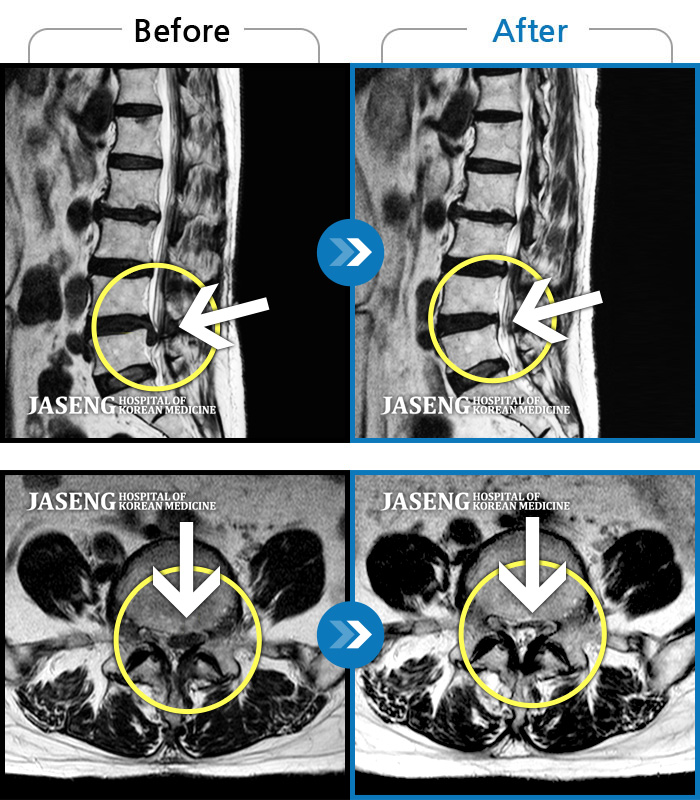

허리디스크

강남 · 강만호 원장

허리통증이 심해서 숙이기 어렵고 차에서 내리기 힘들었습니다.

촬영시기

2021.01.06 ~ 2025.03.10

2025.03.20